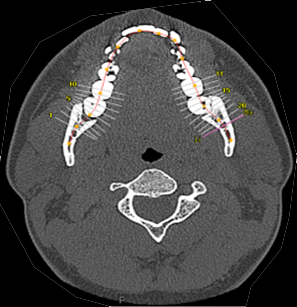

歯科解析ソフト

歯列弓に沿ったパノラマ像やクロスカット像を作成します。CTにて上顎、下顎骨の状態、神経の位置、根尖情報などの把握が可能です。また、画像に対して距離・角度の計測も可能となります。